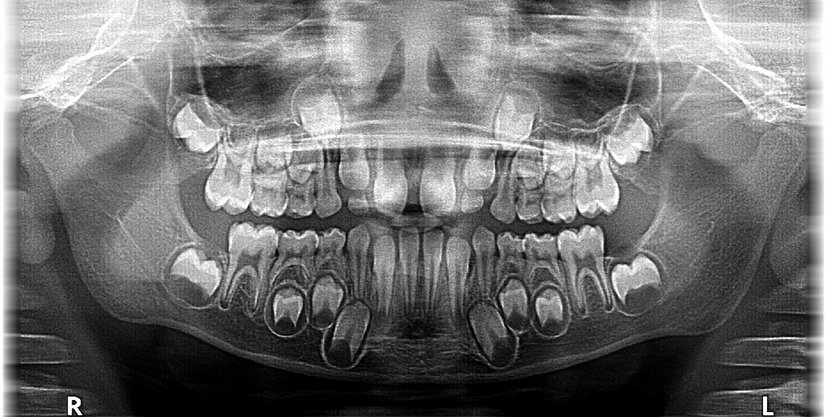

Dişler, henüz insanlar doğmadan önce gelişmeye başlar. Bebekler doğduklarında süt dişleri diş etlerinin altında gelişmeye devam eder. Süt dişleri bir yıl içerisinde çıkmaya başlar.

Altıncı yaştan itibaren çocukların hem süt dişleri hem de kalıcı dişleri çıkmaya hazırdır. Bütün kalıcı dişler çıktığı zaman, diş çıkarma süreci tamamlanır. Düşen ya da kırılan dişlerin yerine yenisi çıkmaz. Yine de bilim insanları, dişleri yeniden çıkarmanın yollarını aramaktadır.[2]